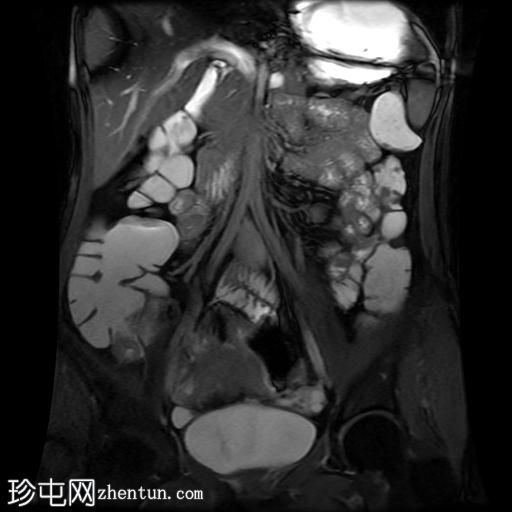

轴位

T2加权像

回肠末端及盆腔回肠肠袢可见长段肠壁增厚及强化,肠周血管丰富,呈“梳状征”,并可见明显的纤维脂肪浸润。

未见瘘管、积液、腹水或梗阻。

磁共振肠道造影(MRE)结果支持克罗恩病的诊断,显示远端及末端回肠以活动

性病

变为主,并可见明显的肠周血管。